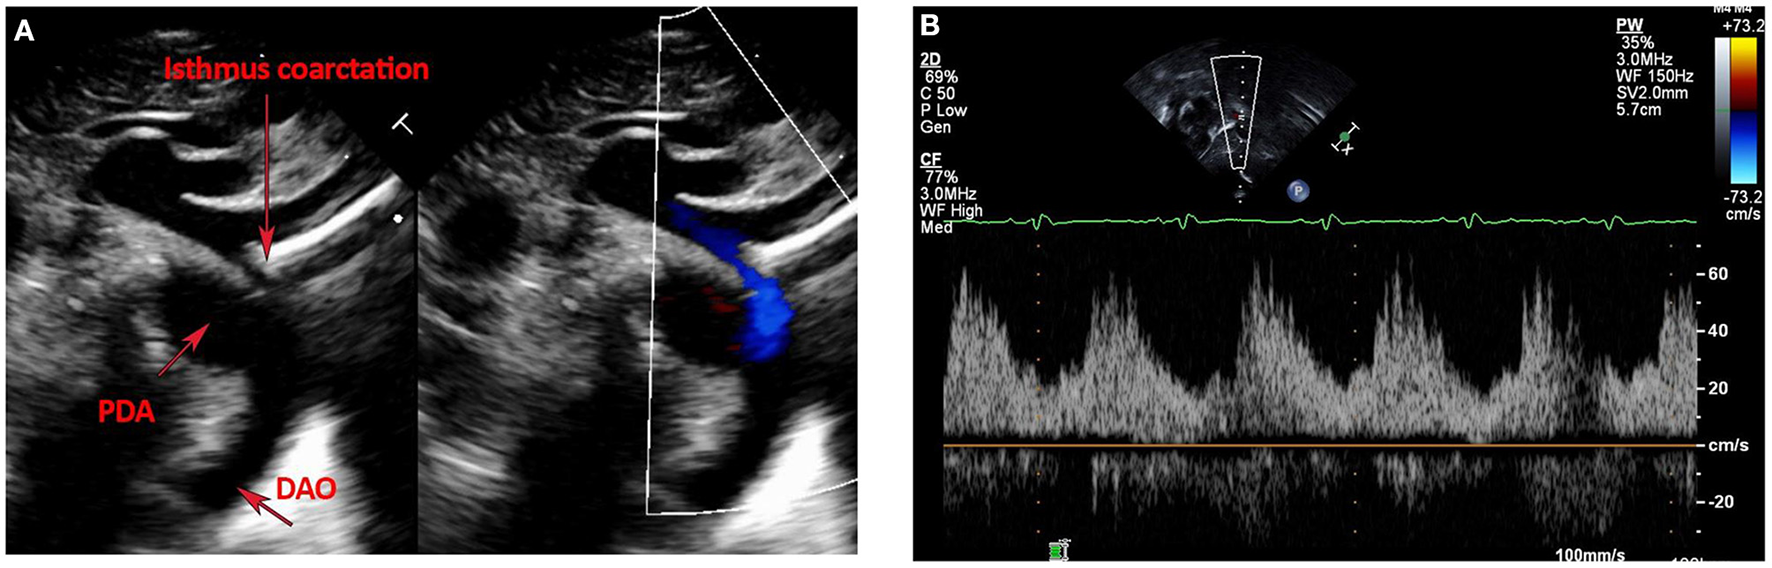

Postnatal echo is the mainstay in diagnosing isolated CoA and associated CHD lesions, in defining the presence, size, and direction of ductal shunting, and in measuring the ascending aorta, transverse arch, isthmus, CoA length and descending aorta dimensions. Echo is safe, readily available, and cost-effective. The suprasternal notch view provides visualization of areas of isolated CoA and allows Doppler gradient measurements (Figure 1A). Delayed systolic peaking with diastolic runoff in the abdominal aortic Doppler flow profile suggests the presence of arch obstruction (Figure 1B).

Figure 1

(A,B) Echocardiographic images of Isolated CoA. (A) Shows B-Mode and color Doppler images of discrete isthmus CoA with obvious size discrepancy between the isthmus and PDA diameters. (B) Shows an abnormal abdominal aorta Doppler profile with a low velocity signal, blunted upstroke with delayed systolic peaking, a slurred downstroke and continuous diastolic flow in a patient with isolated CoA.